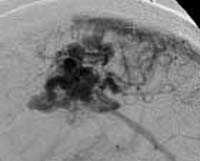

<ÇãÇ÷¼º

³úÁ¹Áß>

ÁÂÃø

Áß³úµ¿¸ÆÀÇ Æó»öÀ¸·Î ÀÎÇÑ ³ú°æ»ö¼Ò°ß(Ç÷°üÁ¶¿µ¼ú»ó

Áß³úµ¿¸ÆÀÌ º¸ÀÌÁö ¾Ê°í ÀÖ´Ù)